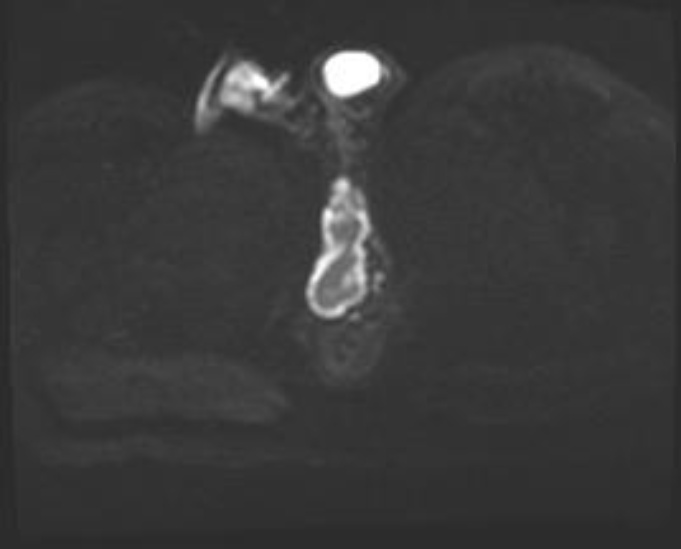

• 3) Imaging: Ultrasound revealed a thickened, edematous scrotal sac with a loculated collection (35 × 10 mm) at the posterolateral aspect, suggestive of cellulitis and abscess formation [3]. MRI confirmed an irregular fluid collection within the corpus spongiosum at the level of the superior pubic ramus, extending to the prostatic urethra with intense enhancement of the soft tissues [4]. Figures 1-3 show the pre operative MRI.

Figure 1. Axial T2-weighted pelvic MRI demonstrating a hyperintense periurethral fluid collection within the corpus spongiosum at the penoscrotal junction, consistent with abscess formation.

Figure 3. Axial post-contrast T1-weighted MRI demonstrating peripheral rim enhancement of the periurethral collection, confirming abscess cavity formation with surrounding inflammatory changes.